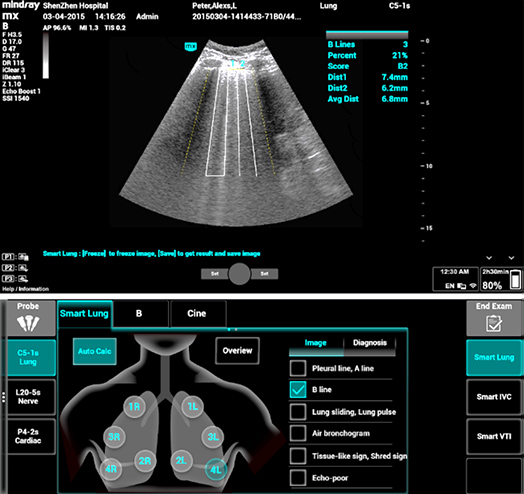

1Smart B-line

Cuenta autom├Īticamente la cantidad de l├Łneas B y el porcentaje del ├Īrea de las l├Łneas B en funci├│n de los protocolos y asigna un puntaje al funcionamiento del pulm├│n en cuatro patrones seg├║n la aireaci├│n pulmonar. La descripci├│n general de la imagen y el mapa a color del puntaje pueden ayudar en la evaluaci├│n de la funci├│n pulmonar.

1